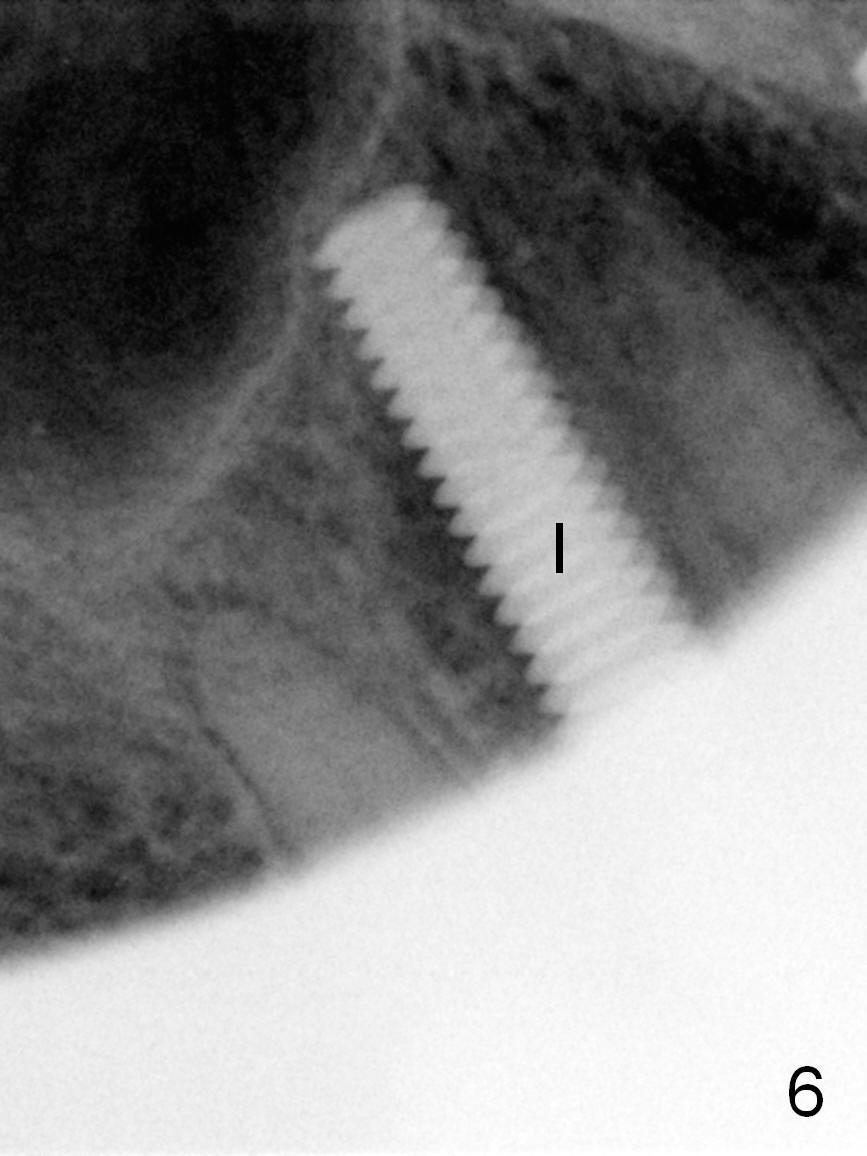

After long discussion, she agrees with extraction and immediate implant.  After the extraction, granulation tissue is removed.  There is buccal apical fenestration.  The socket is treated with Metronidazole.  The socket depth is 17 mm, while osteotomy depth is 20 mm (Fig.4).  A 4x20 mm tissue-level implant is placed with primary stability (Fig.5,6 I).  A short abutment (A) is placed immediately for an immediate provisional.  The buccal gap is filled with Osteogen plug.  There is no crestal bone loss 3 months postop (Fig.7).  The provisional stays in place with occlusal perforation.  The gingiva is healthy 5.5 months post cementation (Fig.8).